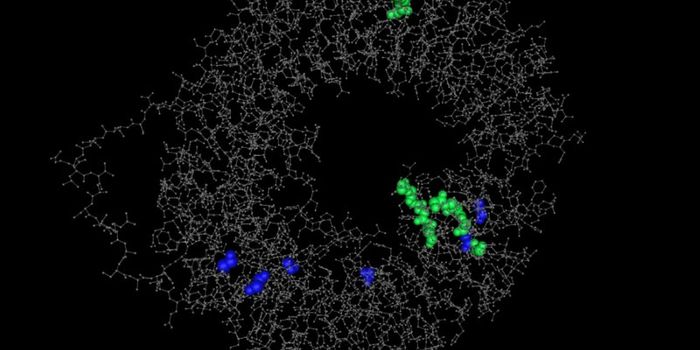

NOV 09, 2021ImmunologyScientists have established the first searchable database of complex immune data, providing the foundations for a new er ...

DEC 21, 2023Drug Discovery & DevelopmentEpigenetic mechanisms responsible for iinitiating HIV latency and creating a long-lived viral reservoirs

SEP 26, 2021Cell & Molecular BiologyHumans can produce millions or even billions of antibodies, so only so many can be captured and screened. But those anti ...

MAY 26, 2020ImmunologyThe immune landscape is staggeringly complex, with a myriad of genetically and functionally distinct immune cell subpopu ...